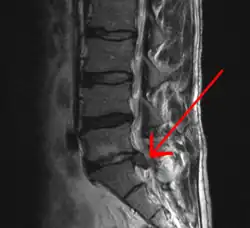

| Imagem de RNM de hérnia de disco lombar (seta) | |

Hérnia de disco/Hérnia discal é a projeção da parte central do disco intervertebral (o núcleo pulposo) para além dos seus limites normais (a parte externa do disco, o ânulo fibroso). Ocorre geralmente póstero-lateralmente, em virtude da falta de ligamentos que sustentem o disco nessa região.[1]

O disco intervertebral é uma placa cartilaginosa que forma uma almofada entre os corpos vertebrais. Após traumatismos (quedas, acidentes automobilísticos, esforços ao levantar, entre outros), a cartilagem pode ser lesada, comprimindo raízes nervosas. Em qualquer local da coluna vertebral pode haver herniação discal.